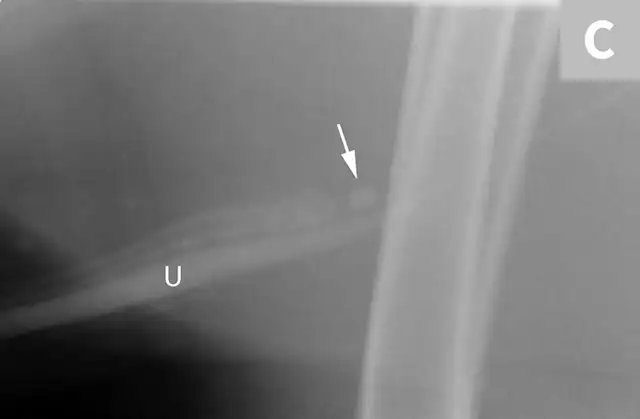

A separate center of ossification associated with the os penis may mimic a urethral calculus (Figure 11 A and B). A separate center of ossification can be seen at either end of the os penis and will be in line with the os penis. A calculus within the penile urethra would be seen ventral to the os penis in the location of the urethra. Contrast urethrography can be a helpful way to differentiate between a separate center of ossification and urethral calculus (Figure 11C).

FIGURE 11A

Lateral radiograph of a male dog collimated to include the urinary bladder and os penis. Note the well-defined mineral opacity just proximal to and at the same level as the base of the os penis—a separate center of ossification (arrow). Also note the two soft tissue opaque nodules summating with the prepuce, presumed to be small nipples (arrowheads).